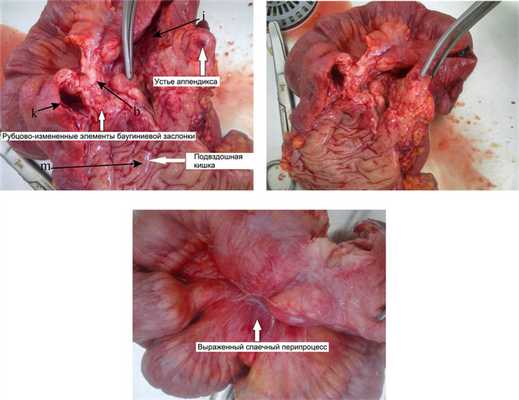

Выполнена лапаротомия, правосторонняя гемиколэктомия с формированием илеотрансверзоанастомоза бок в бок.

Макропрепарат илеоцекальной области представлял собой конгломерат (рис. 3), Рис. 3. Больная Ч., 34 года. Макропрепараты илеоцекального перехода после правосторонней гемиколэктомии. Фото. b — язва; k — просвет восходящей ободочной кишки; i — просвет слепой кишки; m — просвет подвздошной кишки. состоящий из спаянных между собой петель восходящей ободочной, слепой и подвздошной кишок. При рассечении этого участка определялась значительная плотность ткани, деформация стенки, элементы баугиниевой заслонки не дифференцировались, в районе предполагаемой нижней губы баугиниевой заслонки — глубокая язва, неправильной формы, с плотными краями.

Заключение послеоперационного гистологического исследования удаленного макропрепарата илеоцекального перехода (рис. 4): Рис. 4. Больная Ч., 34 года. Микропрепараты илеоцекального перехода. а — лимфоидно-клеточная инфильтрация; b — лимфоидная гиперплазия; с — склерозирование стенки; d — клетки Пирогова—Лангханса; е — крипт-абсцесс; f — язва; k — бокаловидные клетки. Окраска гематоксилином и эозином; ув. 40 (а, б), ув. 100 (в, г). склерозирование всех слоев стенки с выраженной лимфоцитарной инфильтрацией и очаговой лимфоидной гиперплазией. Определяются гигантские клетки Пирогова—Лангханса, крипт-абсцессы, глубокая язва. Количество бокаловидных клеток сохранено. Данная картина соответствует болезни Крона.